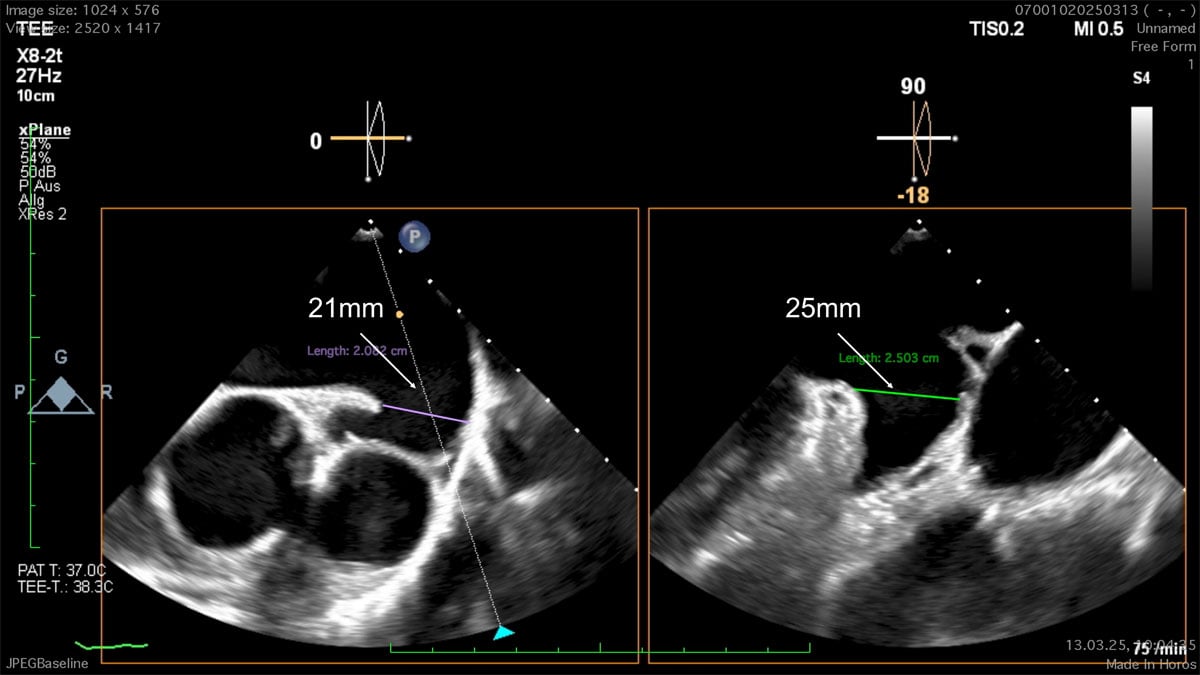

LAA closure - TOE sizing 0°/90°

LAA closure - sizing 0°/90°

"Sandwich technique" for 2-disc devices

Device size is determined by disc size

Given the elevated thromboembolic risk with paroxysmal atrial fibrillation and GI bleeding under DOAC, the decision was made to plan a left atrial appendage occlusion followed by dual antiplatelet therapy for 3 months. A CT and a TOE was performed in this case for planning the procedure, as CT revealed a challenging morphology for both single- and double-disc devices with a shallow LAA (15mm depth) and an inferior-bend chicken wing morphology.

We have a chicken wing left atrial appendage morphology, with a landing zone maximum diameter within the 25-26 mm range, according to imaging tests. In these anatomies, I use to carefully assess the ostium diameters, which are not provided in this case, and I choose a disc approximately 10 mm larger in diameter than the ostium to ensure a complete seal, if the surrounding structures allow it. If using the Amulet device, the most appropriate implantation in this case would be obtained by a semi-sandwich technique, with a 31 mm device and a 38 mm disc. Again, this last aspect is crucial in this scenario to ensure a proper seal.